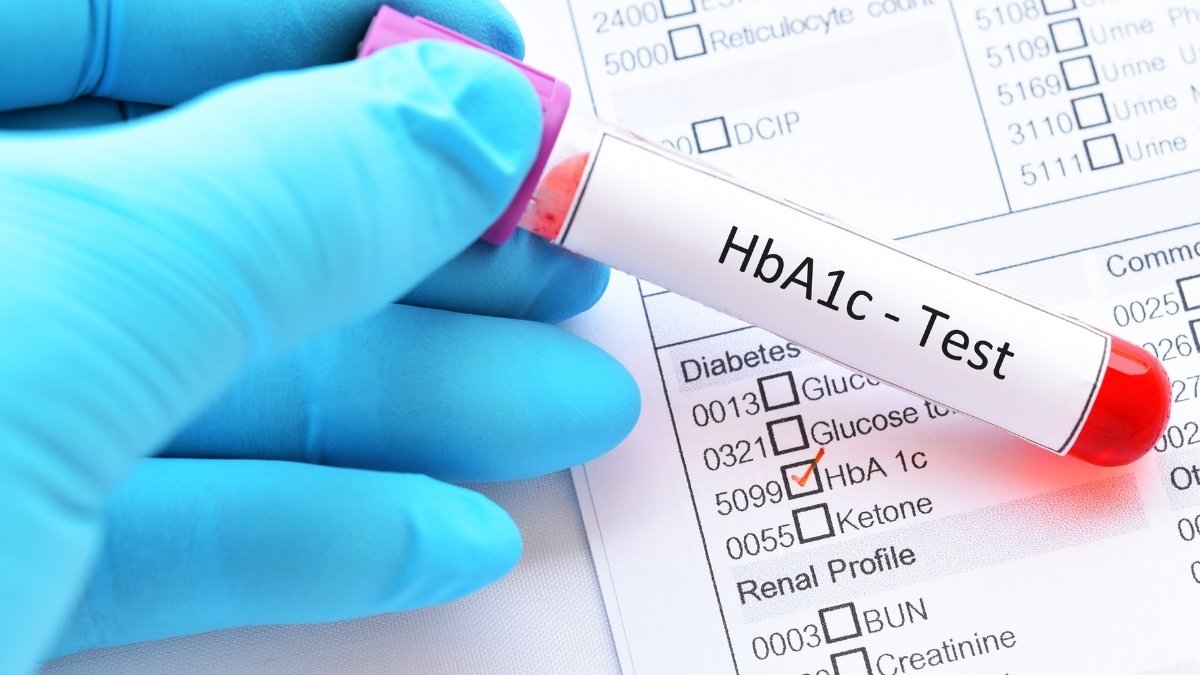

HbA1c measures your 3-month average blood sugar. Lower is better for joints. Continuous glucose monitors help you see patterns. You’ll spot foods that spike your sugar.

The best time to act is before damage begins. Prediabetes is your critical window. This is when fasting glucose sits between 100-125 mg/dL. You’re not diabetic yet. But your joints are already at risk.

Early screening catches problems before they’re visible on X-rays. Check your fasting glucose. Measure inflammatory markers like hs-CRP. Get a lipid panel. These simple blood tests reveal your risk level.

- □ Fasting glucose over 100 mg/dL

- □ Post-meal blood sugar spikes